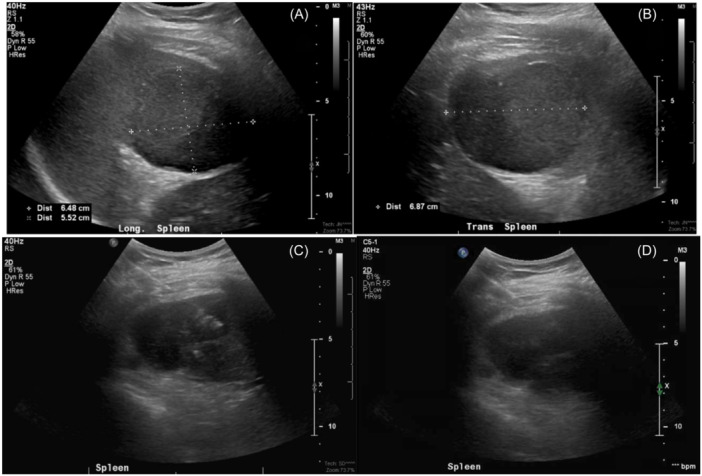

Salmonella splenic abscess.